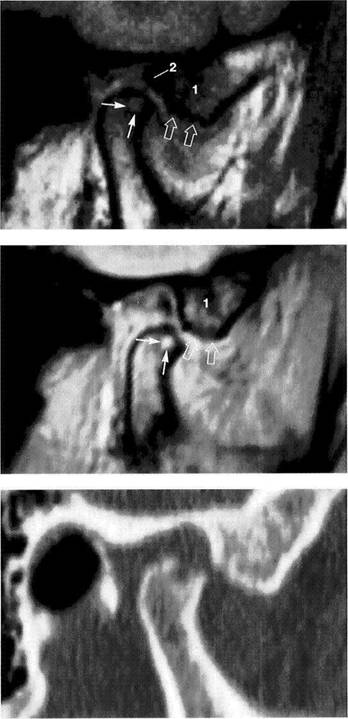

Disk Position in the Frontal Plane

The lateral and medial portions of the joint are evaluated in an MR image made in the frontal plane with the jaws closed (Brooks and Westesson 1993). Angling the frontal plane so that it is parallel with the long axis of the targeted condyle will improve the quality of the image (Westesson 1993). The position of the disk should be determined by using a slice through the pars posterior because the other parts of the disk cannot be as well depicted due to their thinness. When healthy subjects were studied, 1.8% were found to have disks displaced laterally, and 0.9% medially. Among tem­poromandibular joint patients the incidence rose to 4.5% for

lateral and 4.1% for medial disk displacements (Tasaki and Westesson 1993). A macroscopic study of anatomical speci­mens found similar values (3% lateral, 5% medial; Chris­tiansen and Thompson 1990). Incorrect angulation of the frontal plane can give a false picture of a lateral displace­ment (angulation too small) or medial displacement (angu­lation too large) of the disk and thereby lead to an incorrect interpretation and a different set of percentage figures (Khoury and Dolan 1986, Katzberg et al. 1988, Schwaighofer et al. 1990, Hugger et al. 1993).

Physiological disk position

Left: Schematic drawing illustrating normal disk position in the frontal plane.

Right: MRI of the right temporo­mandibular joint of a 24-year-old man. The frontal plane is angled so that it is parallel with the long axis of the condyle. With the jaws closed, the pars posterior of the disk is centered over the condyle.

Medial disk displacement

Left: Schematic drawing of a medial disk displacement in the frontal plane.

Right: MRI of the right temporo­mandibular joint of a 24-year-old patient. An adequate diagnosis of lateral and medial disk displace­ments cannot be made with arthrography and arthrotomogra-phy alone (Kurita et al. 1992a,b).

Lateral disk displacement

Left: Schematic drawing of a lateral disk displacement in the frontal plane.

Right: MRI of the right temporo­mandibular joint of a 23-year-old woman who sustained a fracture of the neck of the condyle at age 14 years. The condyle was tipped medially and has healed in an ab­normal position. The lateral disk displacement is causing pain and recurring limitation of jaw opening.